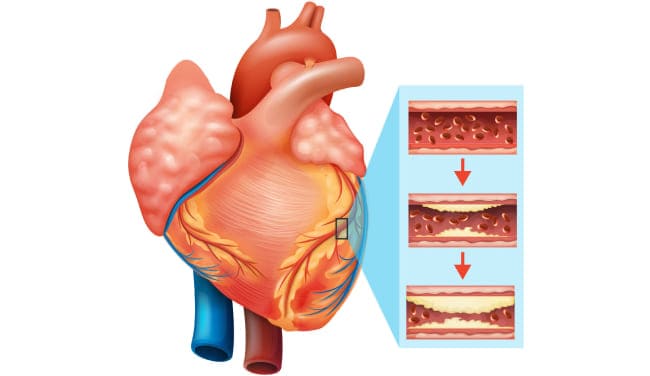

Todos saben que el colesterol es malo. Es él quien obstruye nuestros vasos sanguíneos, los estrecha e interrumpe la circulación sanguínea. Pero no es la única causa, ¿verdad?

Colesterol

Sí, tienes razón. Las placas de colesterol o "placas ateroscleróticas" representan aproximadamente el 65-70% de la contaminación vascular.

A los 50 años, hasta 5 kg de placas de colesterol se acumulan en los vasos de una persona. Estas placas estrechan el lumen de los vasos de 4 a 5 veces.

Imagínate. Si el lumen normal de un vaso es del tamaño de tu dedo, entonces 5 kg de placas de colesterol reducen el lumen al tamaño de 4 fósforos.

Las placas de colesterol por sí solas no son mortales. Sí, la calidad de vida disminuye, la presión arterial aumenta, hay dolores de cabeza y dolor en las articulaciones, debilidad y apatía. Mucho más peligrosas son las masas trombóticas y los cristales de calcio, que también se acumulan en nuestros vasos.